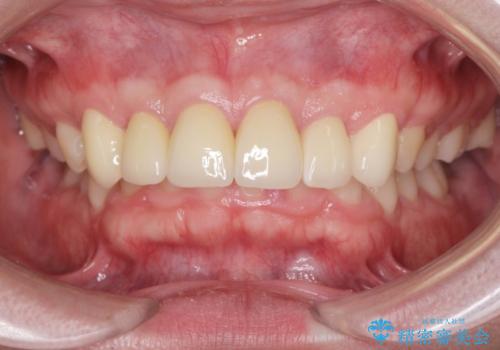

歯周外科を行い、歯ぐきの状態を整えた前歯セラミック治療

- 95.7万円(ジルコニアクラウン×6・仮歯×6・歯周外科 )費用は治療当時の料金となります

歯周外科を行ったことで、歯ぐきの形態や腫れが改善され、審美性だけでなく清掃性も大きく改善することができました。